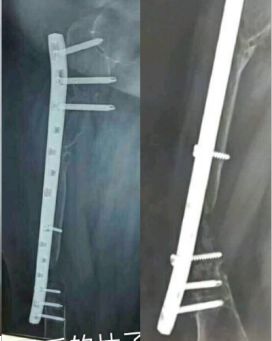

髓内钉与骨的过度处应力集中

应力集中断裂。内固定过于坚强,钉子粗,钢板与过度处应力集中(没有必要手术,必须手术可以用随内针加石膏固定)。